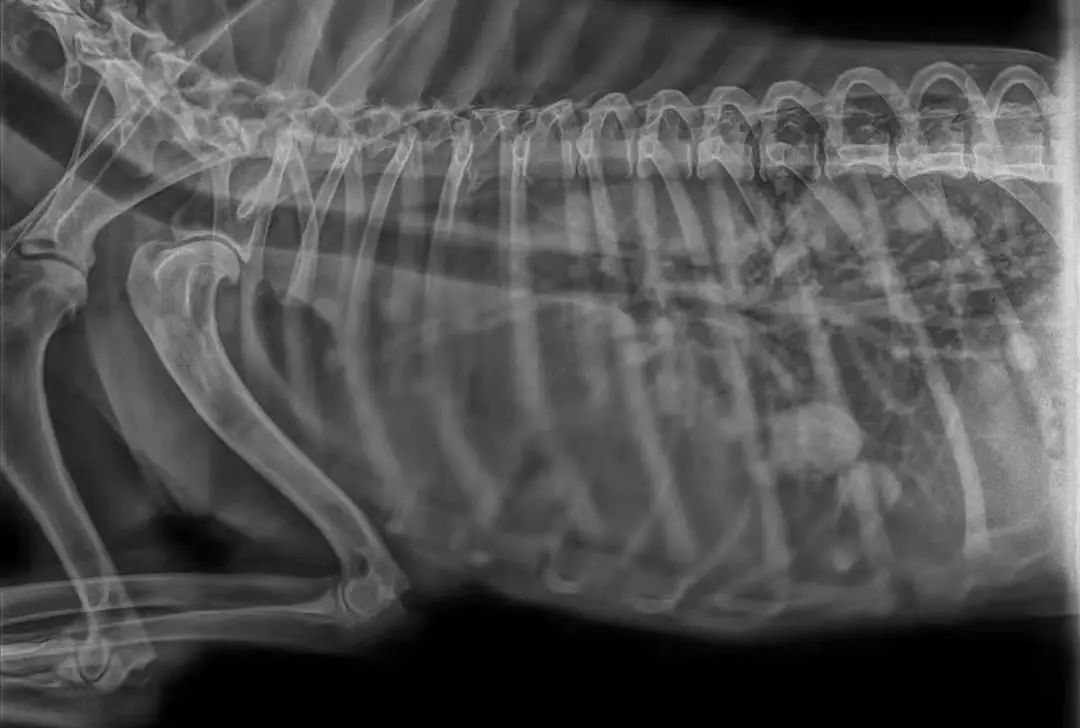

家长说动物干呕了二十天左右,不爱吃饭来就诊,但实际症状为咳嗽,消瘦,当触诊到腹部一个拳头大乳腺肿瘤的时候,开始怀疑可能乳腺肿瘤发生转移,DR,显示胸腔肿物,胸腔积液,才五岁.....尽早绝育,定期体检很重要↓↓